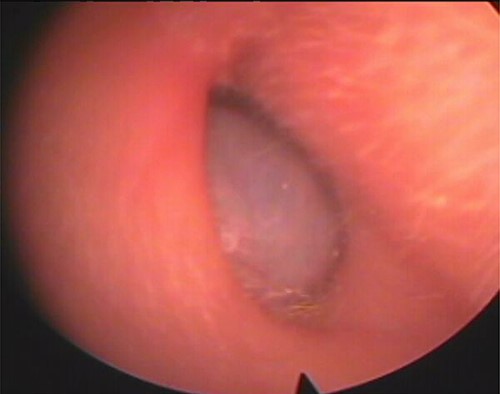

Our patient was a 40-year-old female, with unremarkable disease history, who presented with a fullness of the right ear for 6 months which was associated with progressive hypoacusis and intermittent ipsilateral tinnitus. The clinical examination showed a mass in the right external auditory canal, attached to the posterosuperior wall, which was smooth, pink, firm, mobile, well limited and hemorrhagic on contact (Fig. 1). Weber and Rinne tuning fork tests were negative and right-lateralized, respectively. Preoperative pure tone audiometry revealed an average right conductive hearing loss of 37.5 dB. Imaging based on computed tomography (CT) scan showed a mass occupying the outer two-thirds of the right external auditory canal, measuring 17 mm, well limited, with regular contours. The tissue radio density measured was 61 HU with erosion of the middle ear (Fig. 2).

Axial (A) and coronal (B) CT scans showing a tissue lesion process of the external auditory canal with erosion of the eardrum and filling of a few mastoid cells.